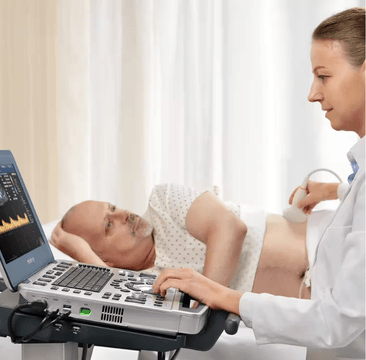

Ultrasound Machines

As the healthcare industry faces pressure to improve patient outcomes and reduce costs, clinicians are turning to ultrasound for a more cost-effective, real-time, and patient-friendly imaging alternative. Mindray North America offers innovative, leading-edge, accessible ultrasound machines that empower you to provide the highest quality of care now and in the future. Experience peace of mind and see something better with Mindray Ultrasound.

Ultrasound is a game-changing solution as the healthcare industry faces pressure to improve patient outcomes and reduce costs. MindrayŌĆÖs cutting-edge ultrasound machines offer a more cost-effective, real-time, and patient-friendly imaging alternative, with innovative technologies that can help improve patient outcomes and reduce costs. Explore our range of ultrasound machines, tailored to meet the needs of various medical departments.

Why Choose Mindray for Your Ultrasound Needs?

Mindray is dedicated to providing world-class solutions that meet the clinical and financial needs for a diverse range of healthcare institutions. Through it all, we are steadfast in our vision to provide better healthcare for all. Here's why leading healthcare providers nationwide source their ultrasound systems from us.

Partner With Us for Advanced Ultrasound Solutions

Trust Mindray Ultrasound Machines for high-quality, leading-edge imaging performance. With pioneering diagnostic capabilities and technology that evolves to meet dynamic healthcare requirements, our solutions empower healthcare providers to meet patient needs and improve care quality.

Submit an online contact form to explore how our solutions can enhance your efficiency and excellence in patient care.?